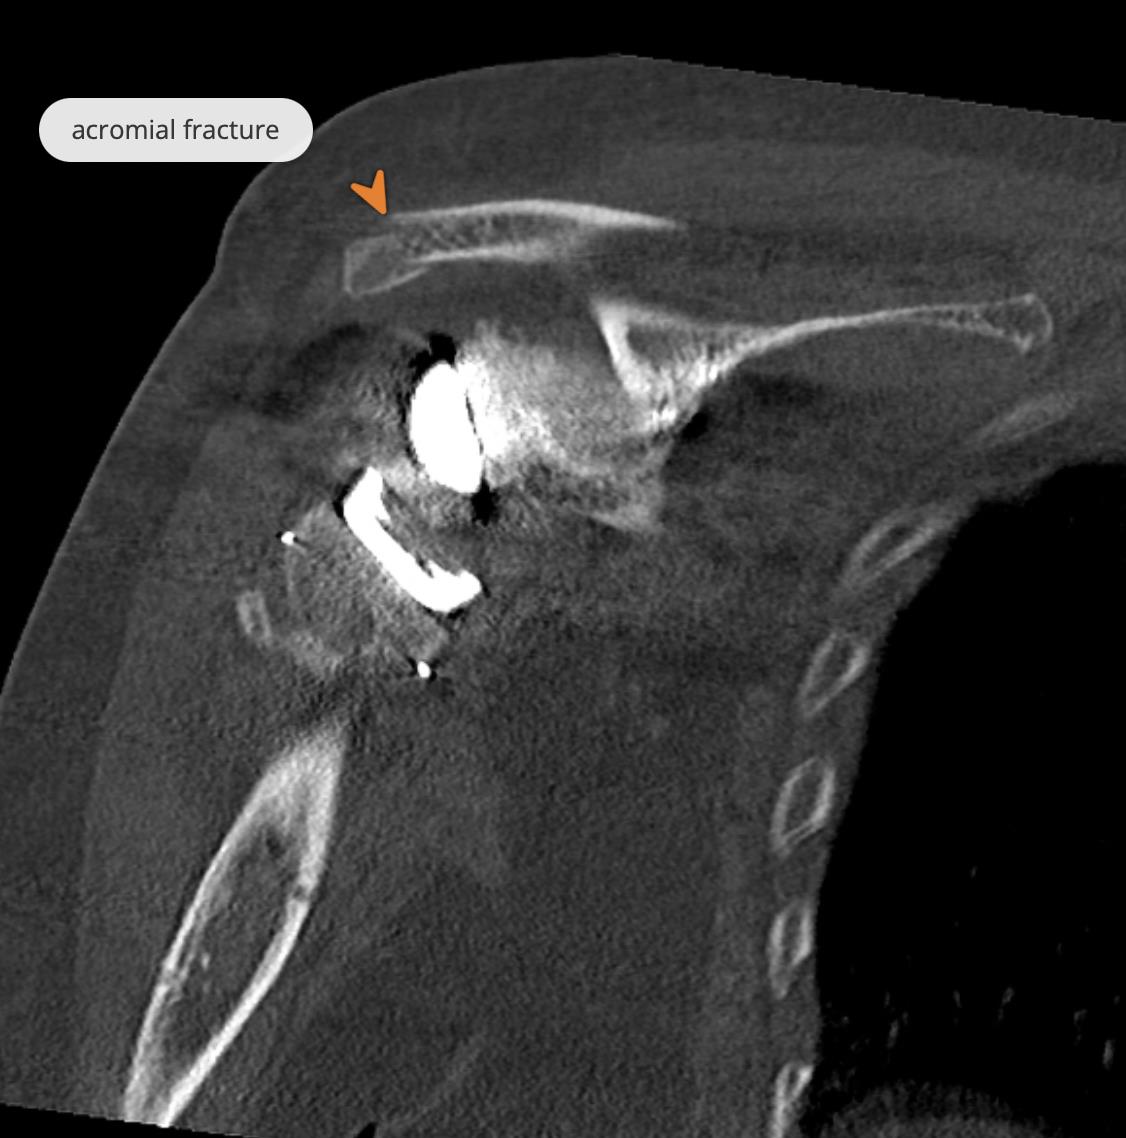

The patient had a reverse total shoulder arthroplasty with an onlay humeral component performed for rotator cuff tear arthropathy, which was complicated by an acromial stress fracture. This complication occurs because of the deltoid tensioning that allows the implant to compensate for a non-functional rotator cuff, and is more common with an onlay humeral component (Answer choice 3).

Rotator cuff tear arthropathy represents a specific pattern of shoulder degenerative joint disease that results from a rotator cuff tear leading to abnormal glenohumeral wear and subsequent superior migration of the humeral head. Treatment for minimally symptomatic patients involves activity modification, subacromial steroid injections, and physical therapy; however, with progressive pain and deterioration of shoulder function, reverse total shoulder arthroplasty (RSA) is often indicated. By design, RSA moves the center of rotation inferiorly and medial, which improves the mechanical advantage of the deltoid muscle and allows it to act on a longer fulcrum to provide functional elevation of the arm. Given this increased tensioning of the deltoid muscle, increased stresses are placed across its origins on the scapular spine and acromion, predisposing to post-operative stress fractures. Though not extremely common, they occur with an incidence of ~4-5% at a mean of 9 months postoperatively, with risk factors being osteoporosis, female sex, and a more medialized pre-op center of rotation given functional lateralization post-operatively relative to this initial medialization. Treatment with conservative management leads to union in ~40-50% of cases, with operative management often indicated for nonunion or those with persistent pain.

Figure A is a pre-operative coronal CT image demonstrating the sequelae of rotator cuff tear arthropathy with superior humeral head migration and acromial acetabularization. Figures B-E represent sequential coronal, sagittal, and axial post-operative CT images of a reverse total shoulder arthroplasty with an acromial process fracture. Illustration A demonstrates this fracture with a label.